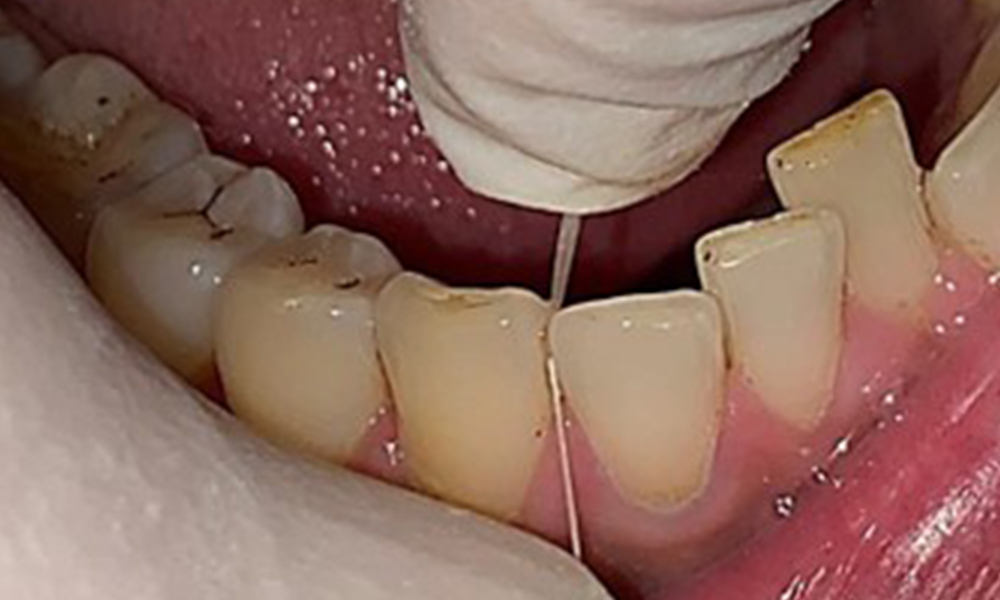

Nahaufnahme der Zähne

Abb. 5: Nahaufnahme der Zähne 45-47. Grüne Pfeile zeigen Attritionen und Erosionen im Bereich der bukkalen Höcker mit partiellem Schmelzverlust, © Dr. R. Krapf

Dental zeigt sich ein vollbezahntes Gebiss mit 28 Zähnen. Auffällig sind Erosionen und Attritionen

(Abb. 4, Abb. 5). Der Patient trägt seit vielen Jahren nachts eine Schiene mit adjustiertem Aufbiss aufgrund Bruxismus. Die Erosionen sind auf den langjährigen Konsum isotonischer Getränke zurückzuführen. Parodontaler Knochenverlust und aktive kariöse Läsionen sind nicht vorhanden.